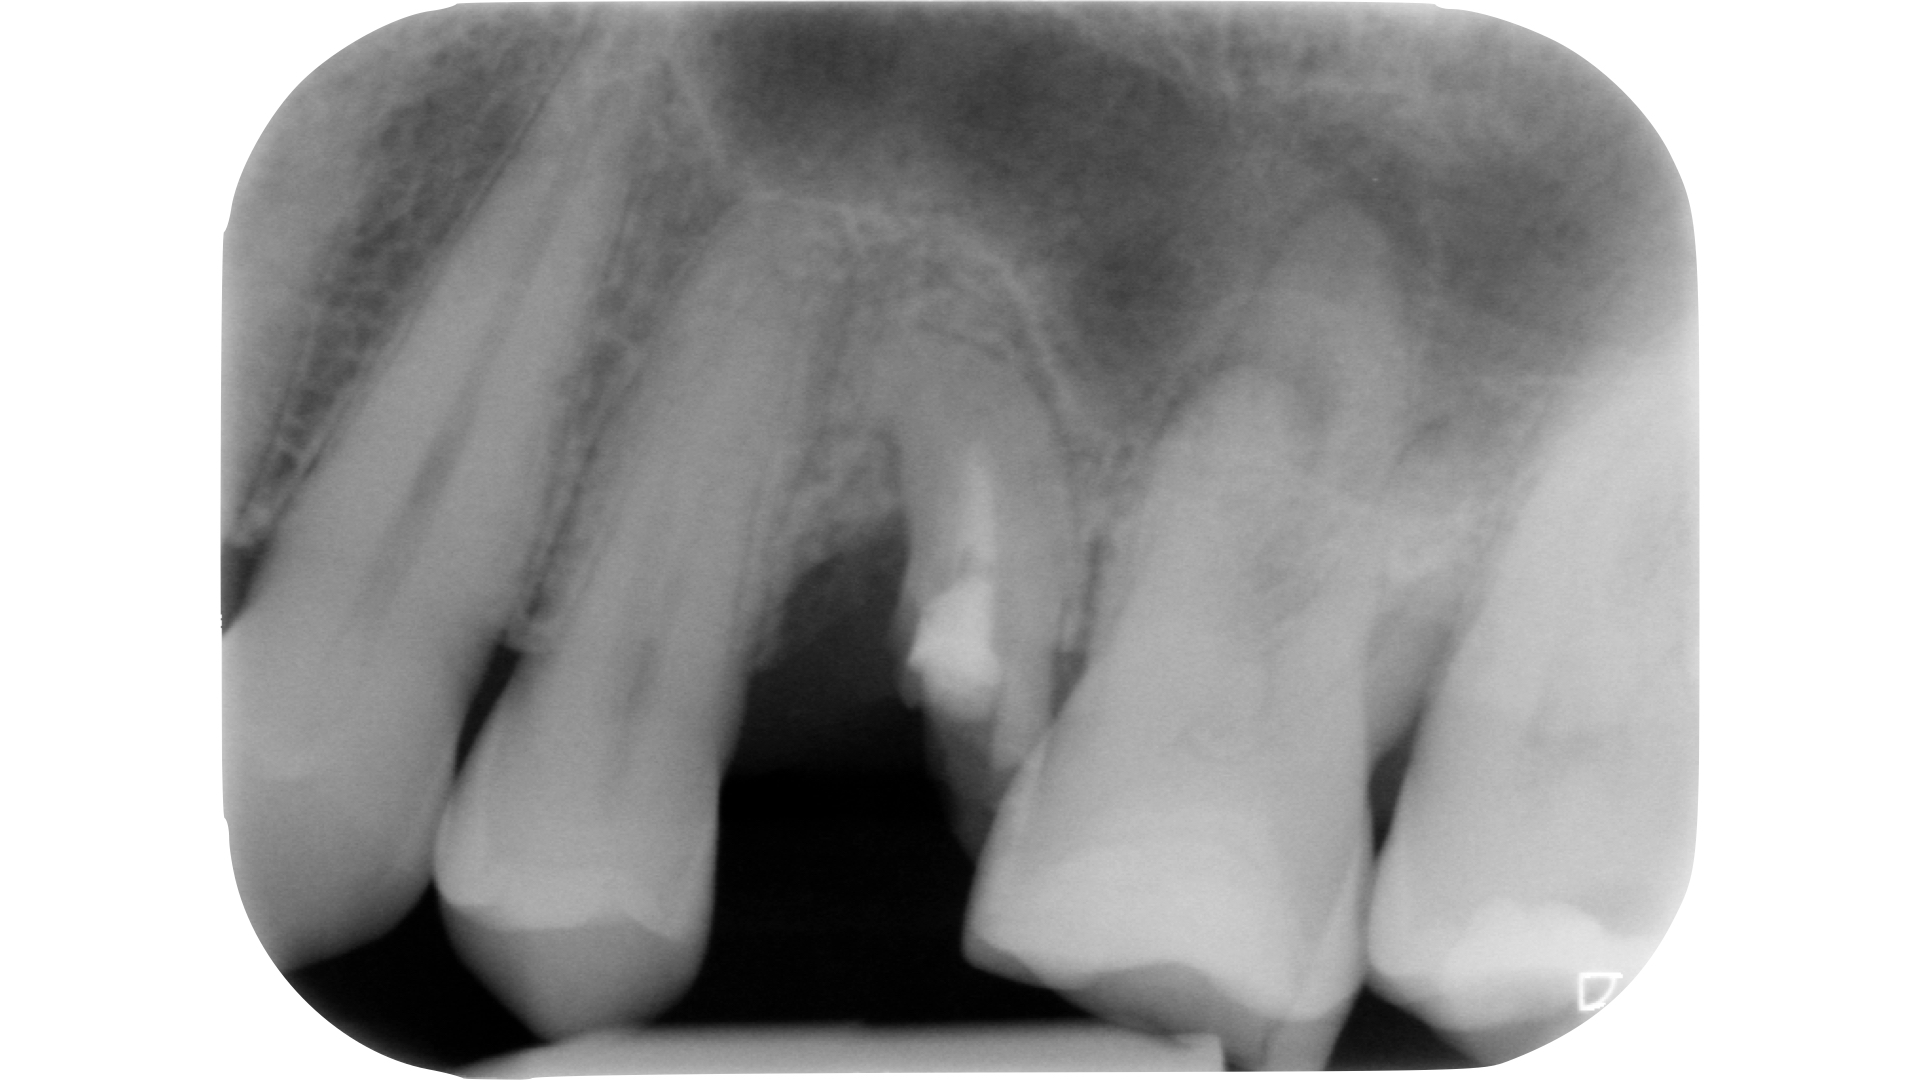

Devono essere valutate con molta attenzione la posizione dell’elemento in arcata e la sua inclinazione (Figure 6-7), l’entità e la posizione del processo carioso se presente, gli eventuali restauri posizionati sul dente e i rapporti con il parodonto: tutte queste considerazioni permetteranno al clinico di capire innanzitutto la mantenibilità e la possibilità di isolare mediante diga di gomma il dente. L’interpretazione degli esami radiografici consentirà inoltre di valutare alcuni parametri preoperatori di notevole importanza:

Un’attenta analisi di questi dati clinici e radiografici consentirà al clinico di ridurre notevolmente il rischio di errori grossolani in questa delicata fase del trattamento.